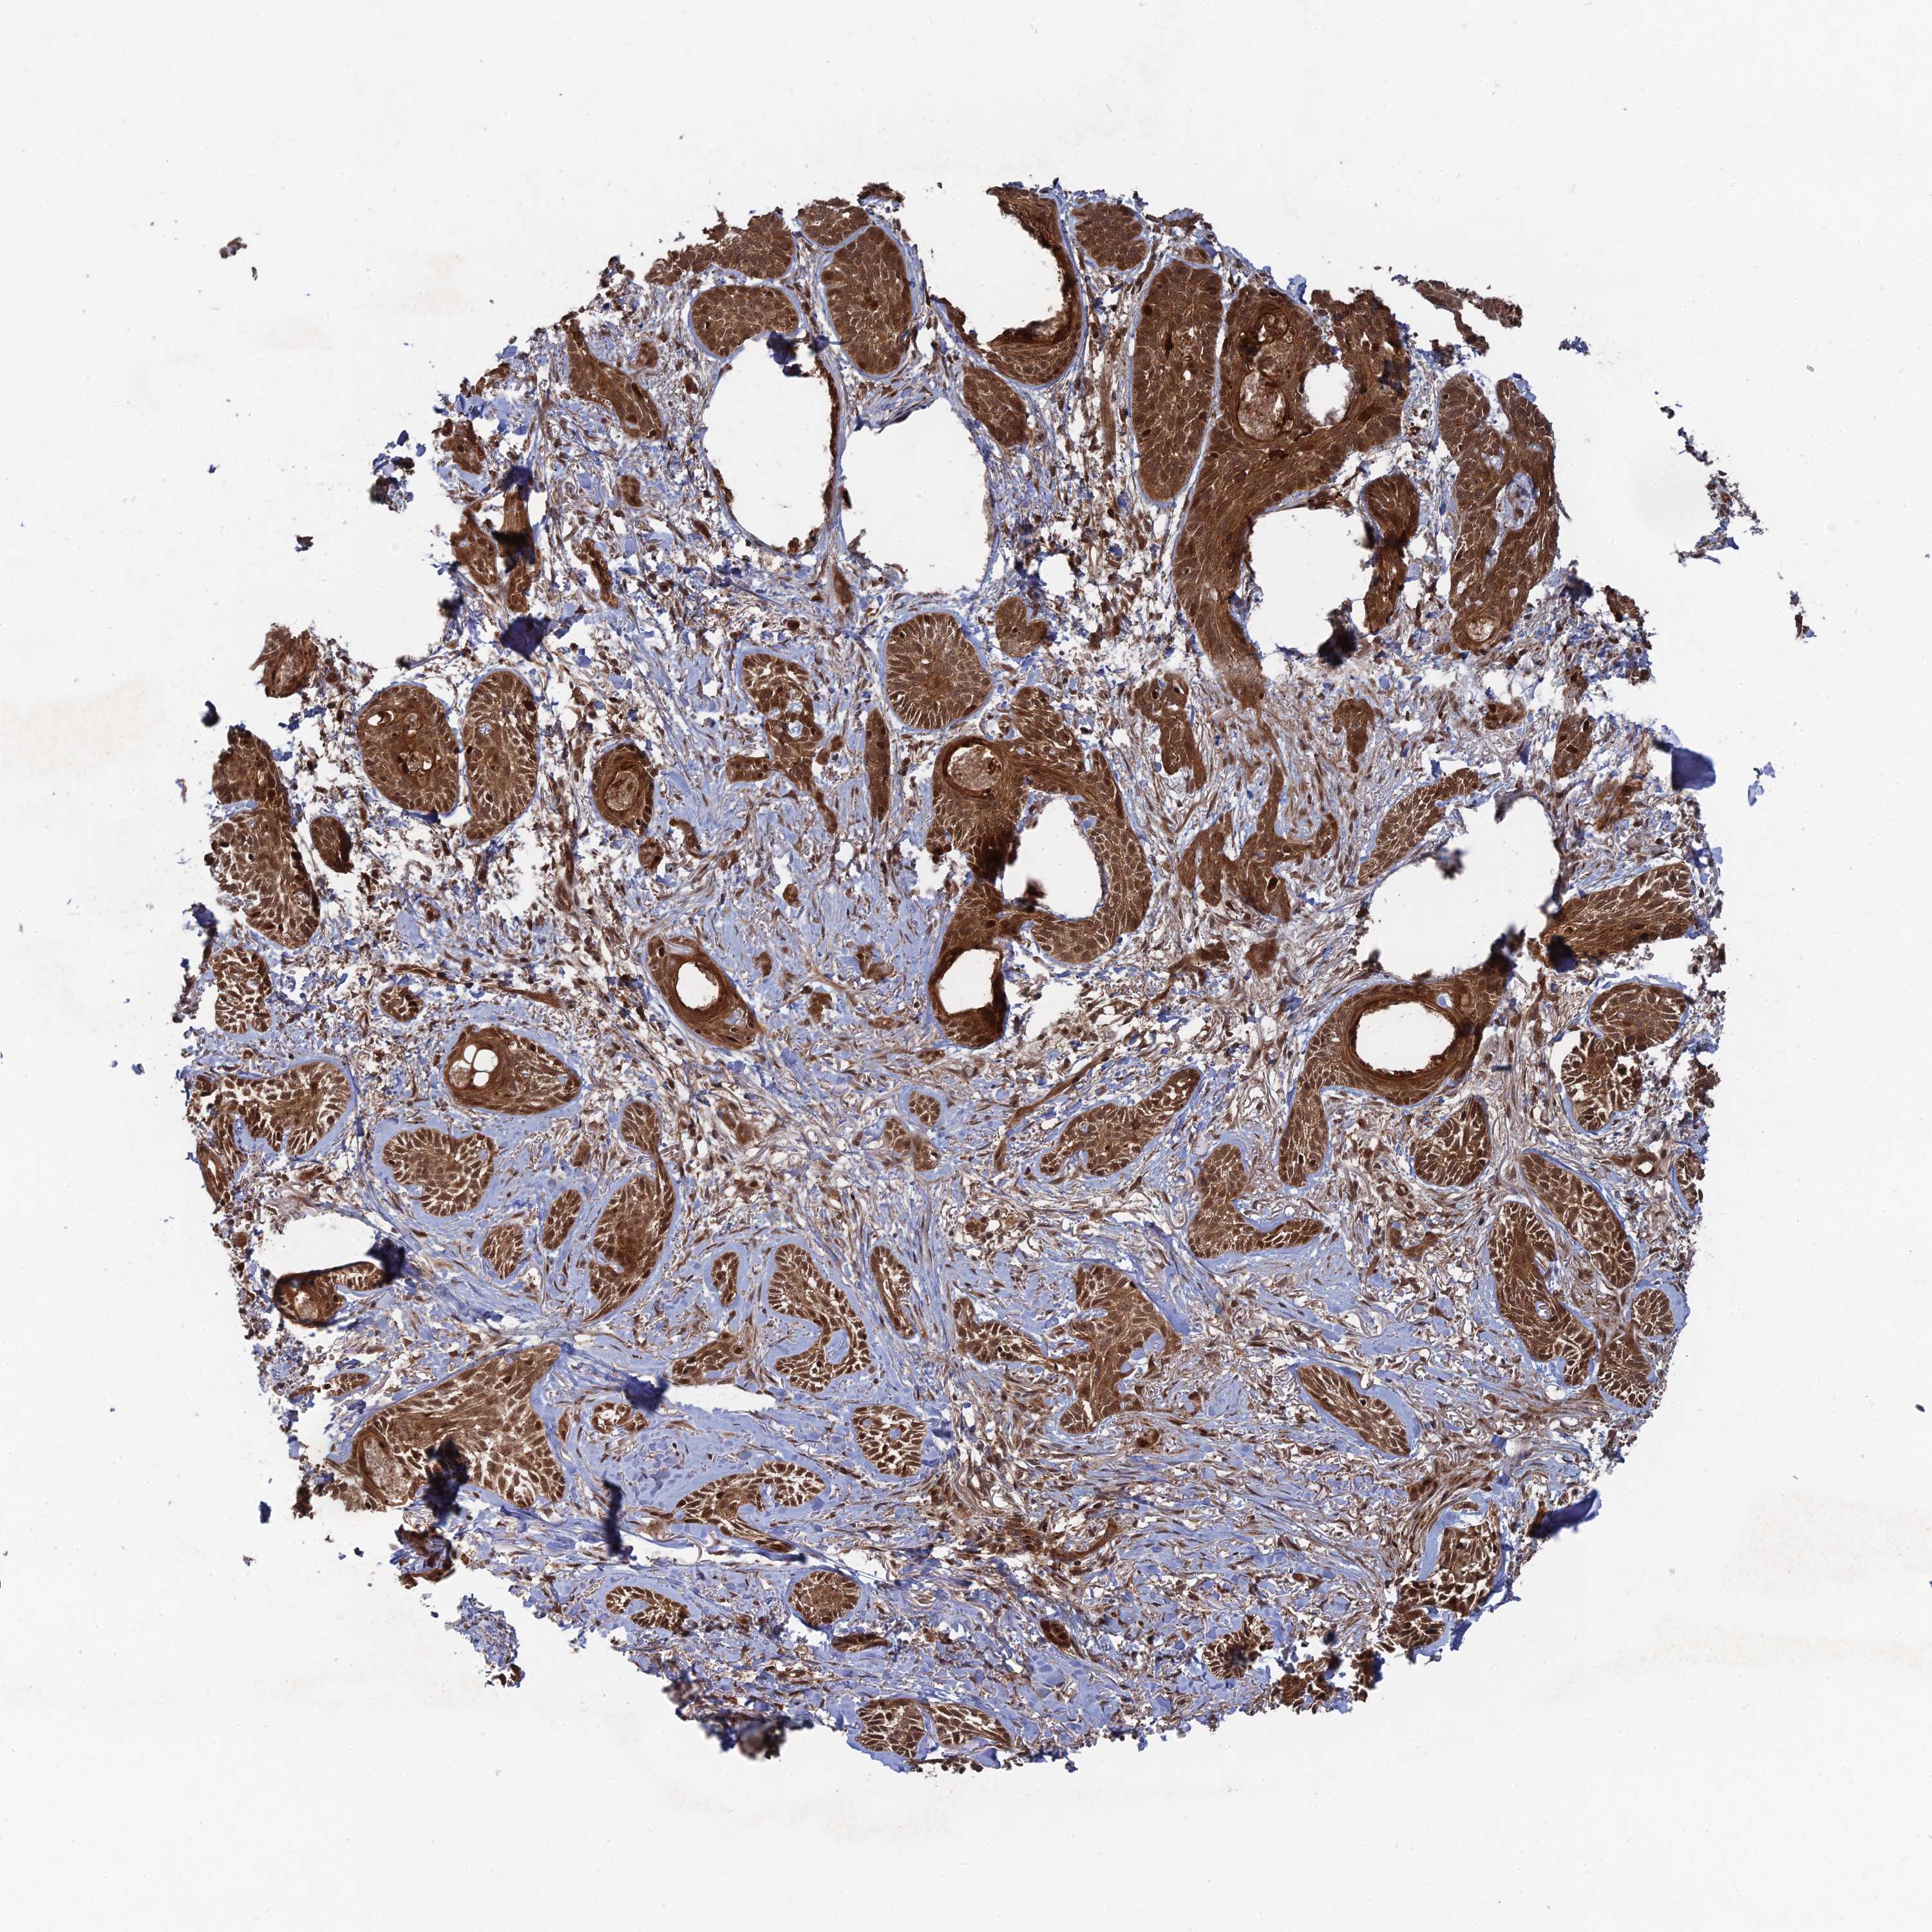

Basal cell and squamous cell cancer

SKIN CANCER - Protein expressioni

A mouse-over function shows sample information and annotation data. Click on an image to view it in a full screen mode. Samples can be filtered based on level of antibody staining by selecting one or several of the following categories: high, medium, low and not detected. The assay and annotation is described here.

Each image is clickable and will lead to virtual microscopy that enables deeper exploration of all samples and also displays staining intensity scores, fraction scores and subcellular localization as well as patient and tissue information for each sample.

Antibody HPA038396

Squamous cell carcinoma, NOS